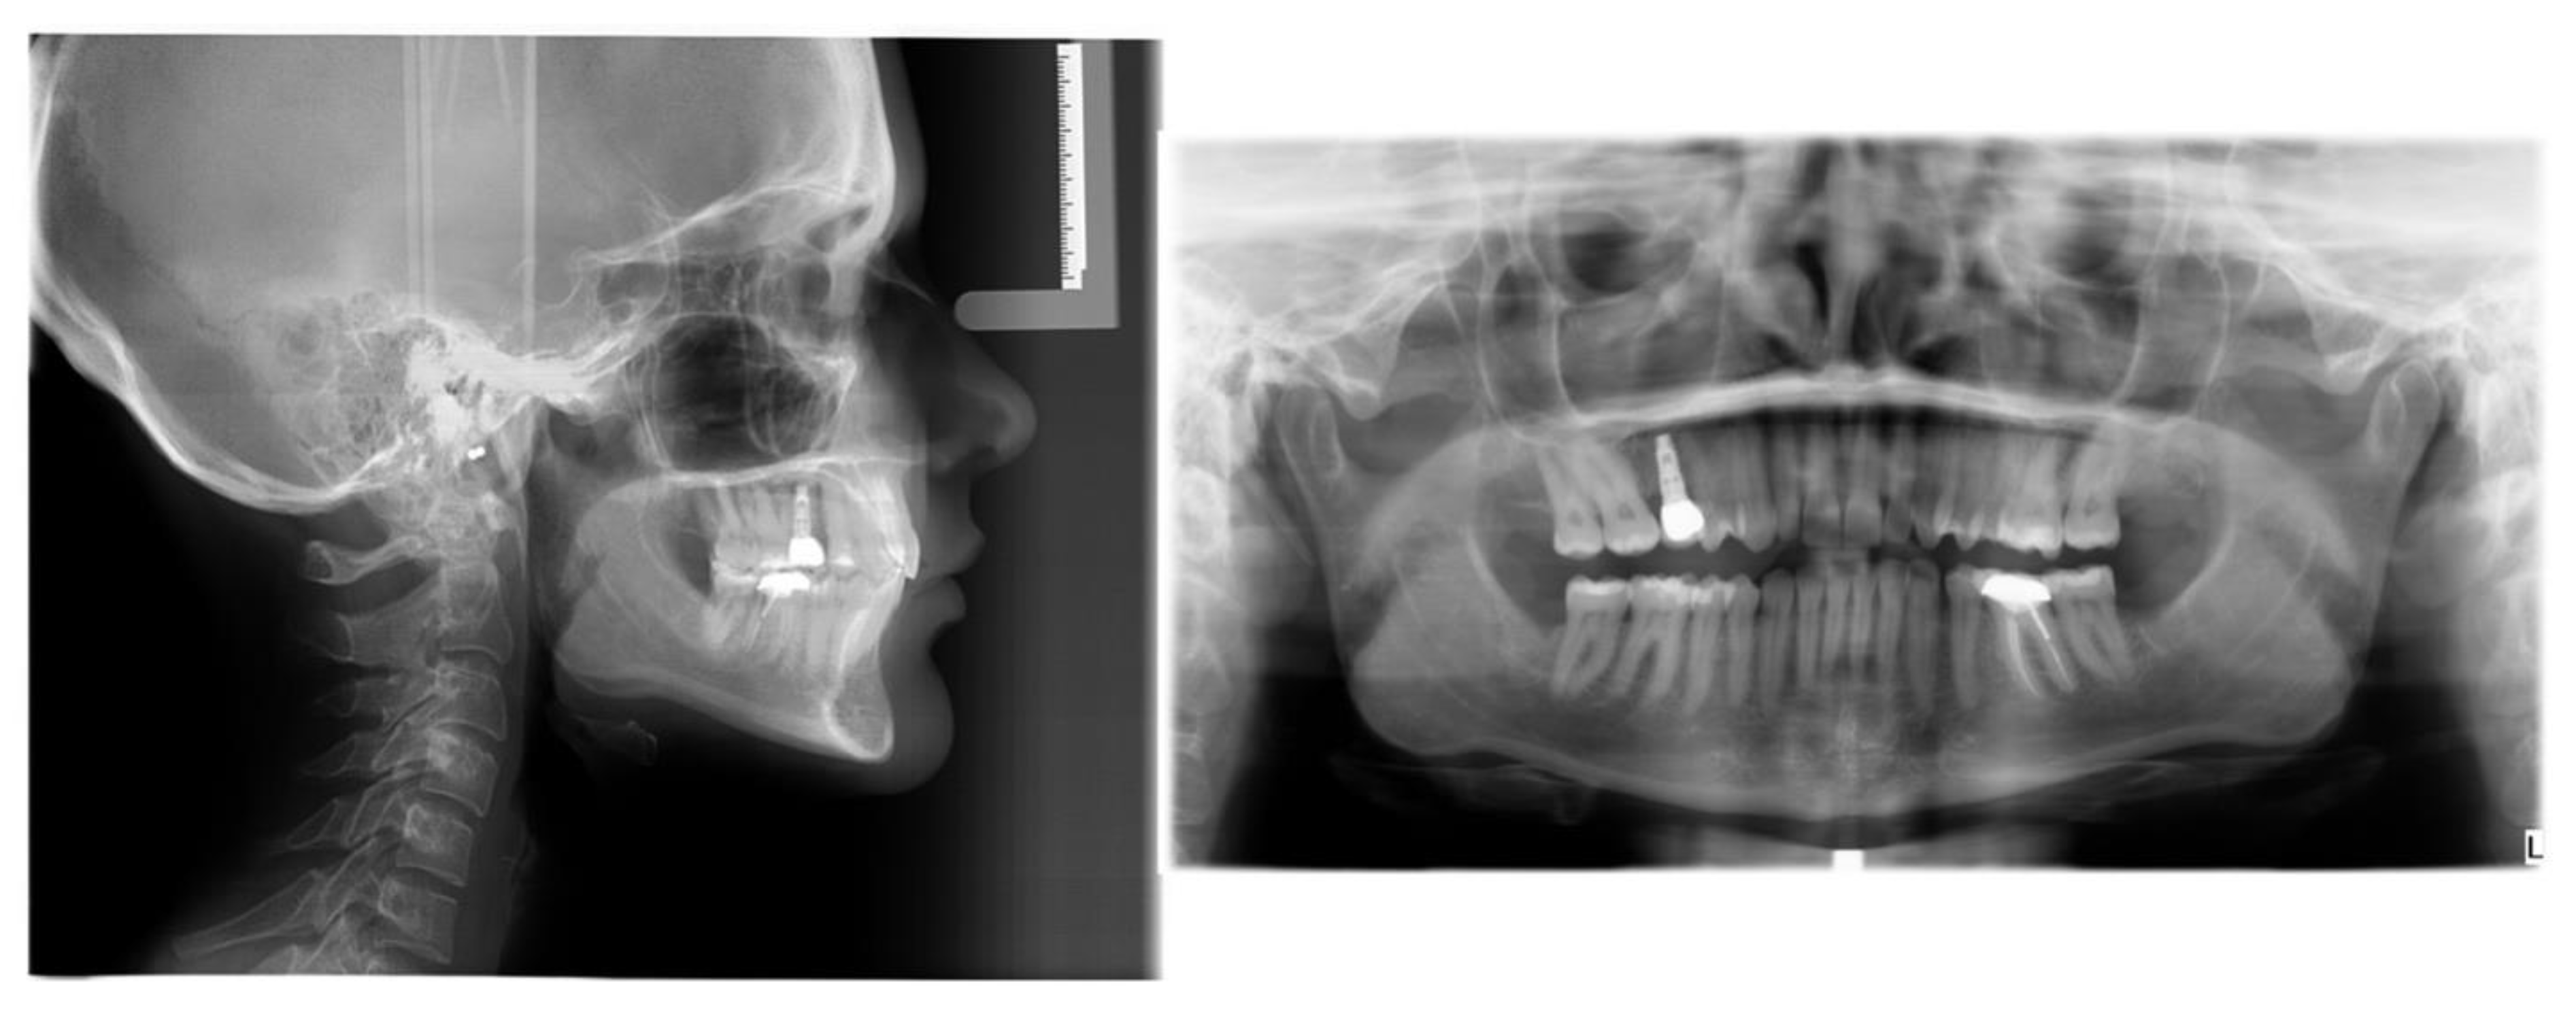

Figure 18. Pre-restorative lateral cephalometric and panoramic radiographs taken in habitual occlusion.